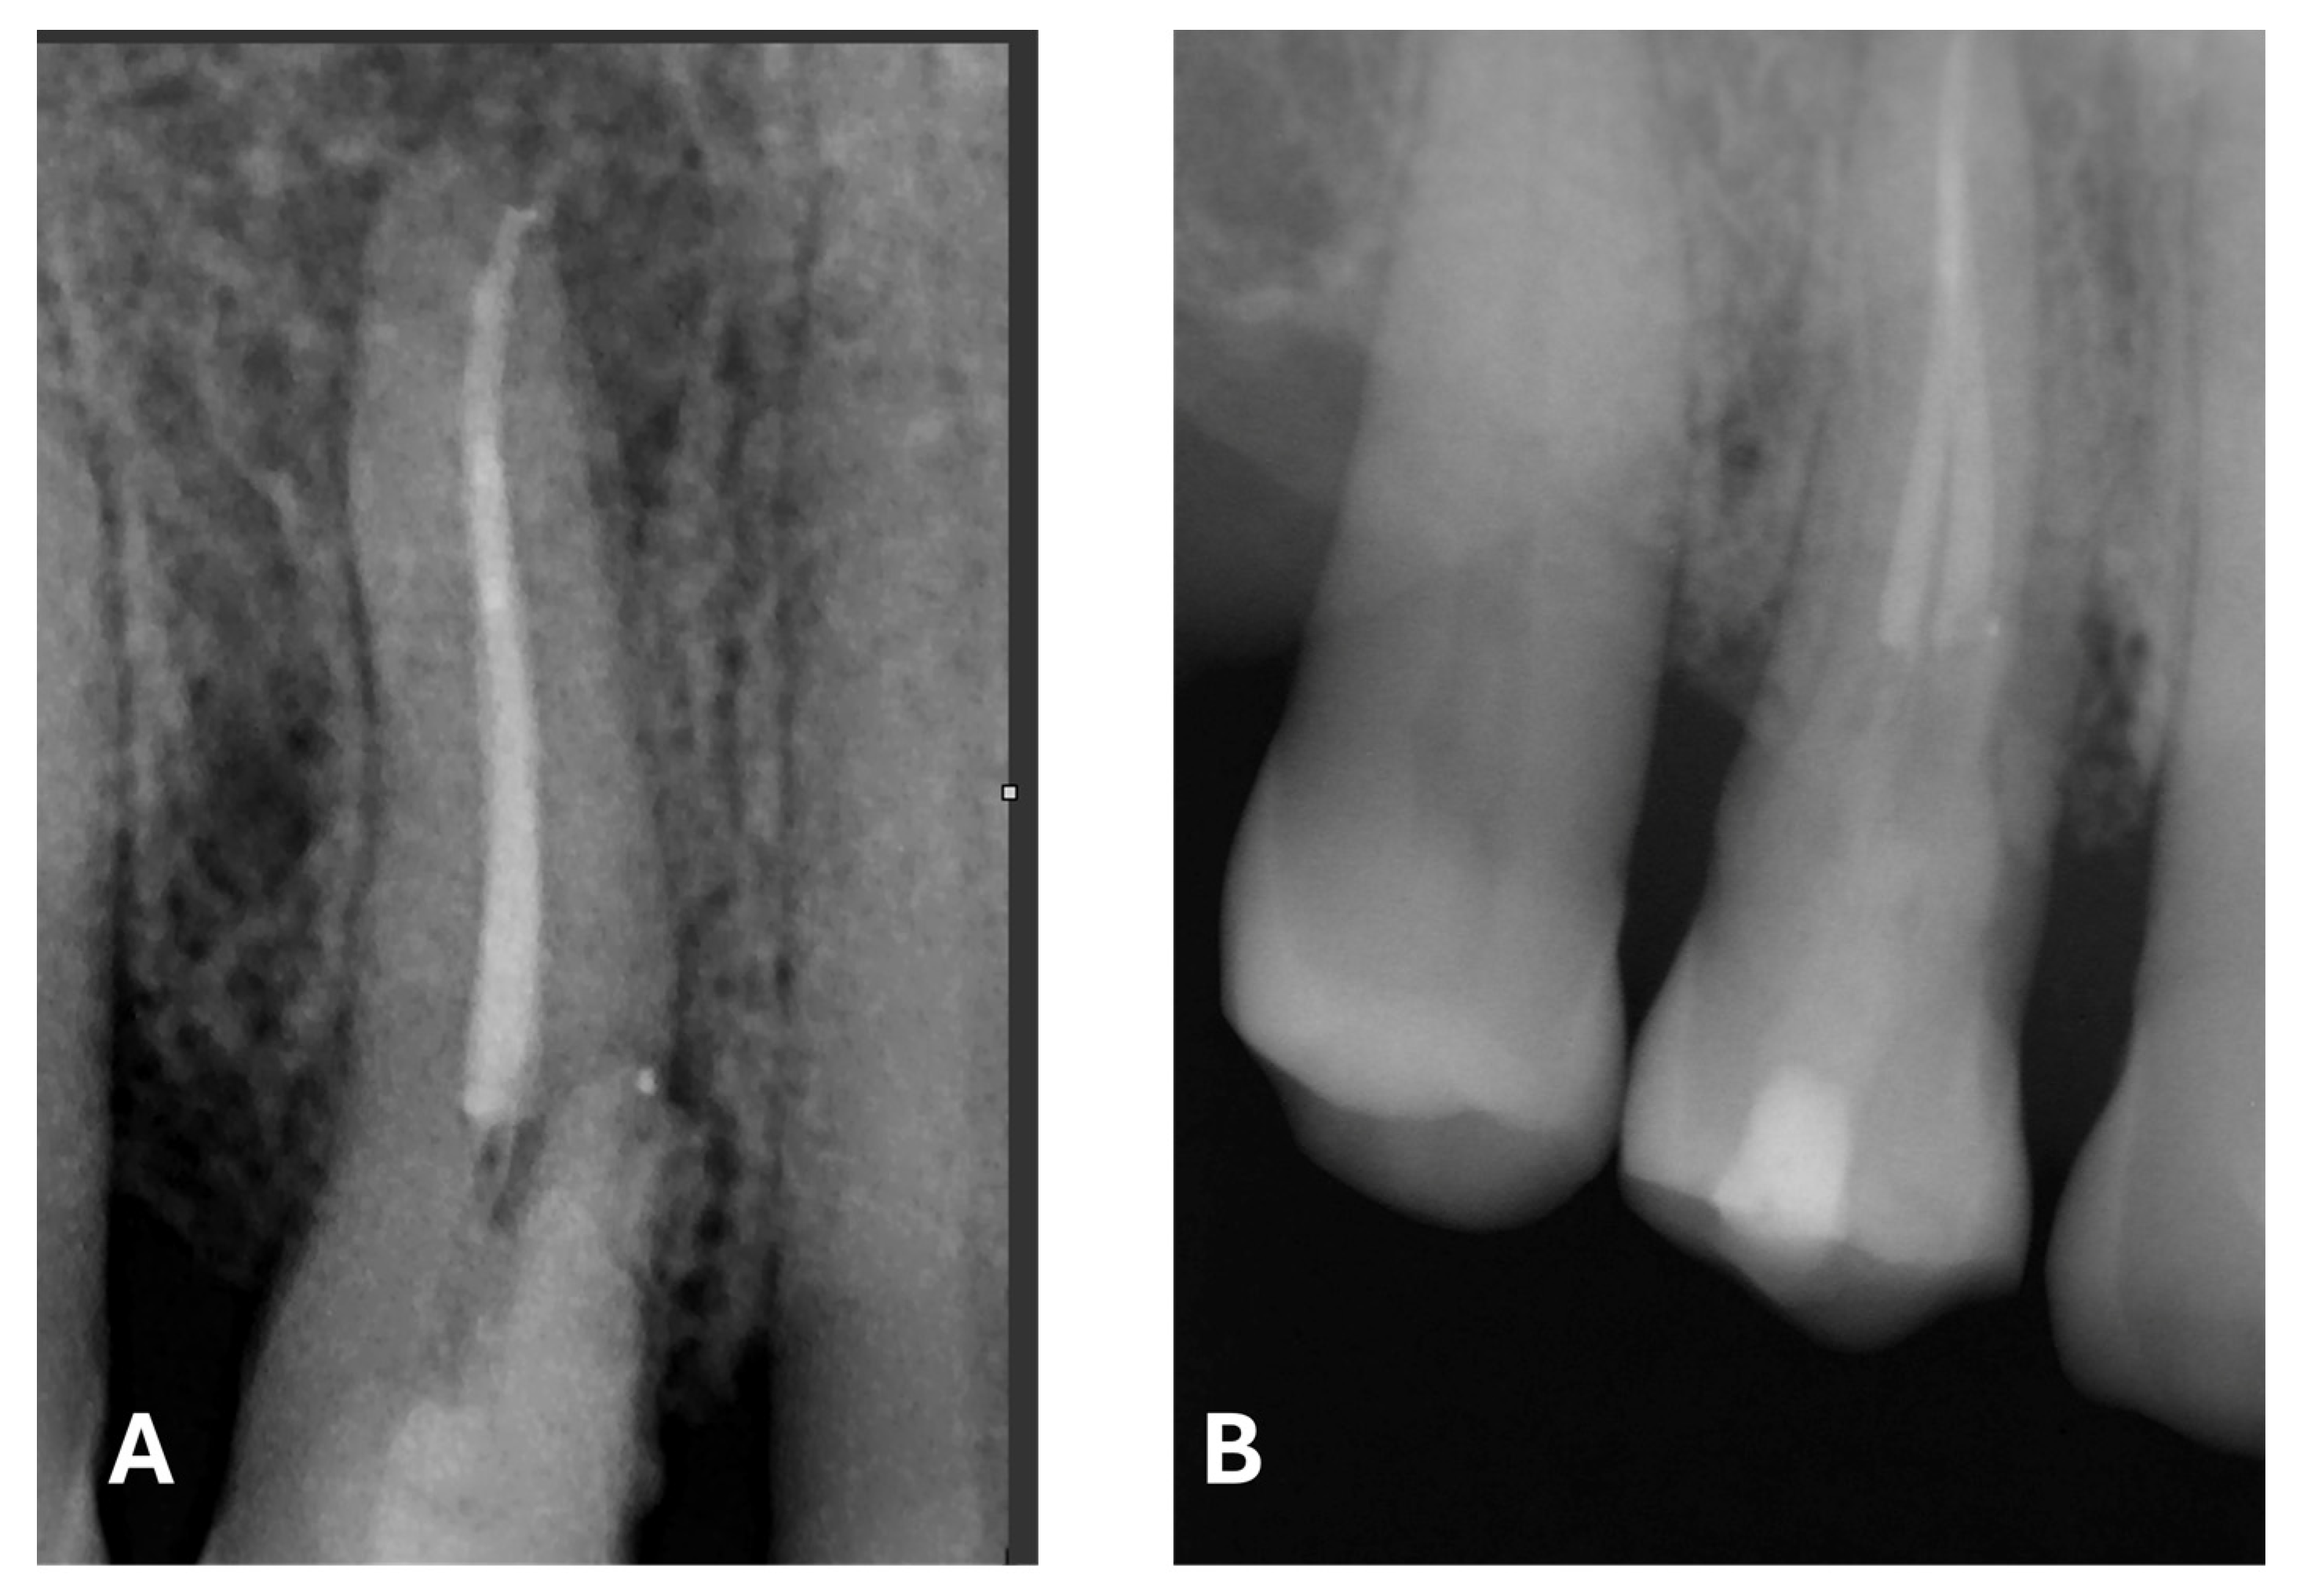

Figure 9.

Post-treatment radiograph with composite filling. (A) focus on the periapical lesion, root canal obturation and Biodentine application. (B) focus on composite filling. Note the radiographic evidence of widening of the lamina dura in the mesiocervical region.

At the 12-month radiographic follow-up, healing of the EPL was confirmed. Restoration of the lamina dura and the periodontal ligament adjacent to the treated site was observed (Figure 16 and Figure 17).

Figure 16.

Intraoral radiography of tooth 1.4 at 12-month follow-up.

Figure 17.

EPL before (A) and after treatment (red circle showing mesiocervical widening of the lamina dura space) (B) and at 12-month follow-up (C) with radiographic evidence of restoration of the lamina dura (green circle), periodontal ligament space and absence of PL.